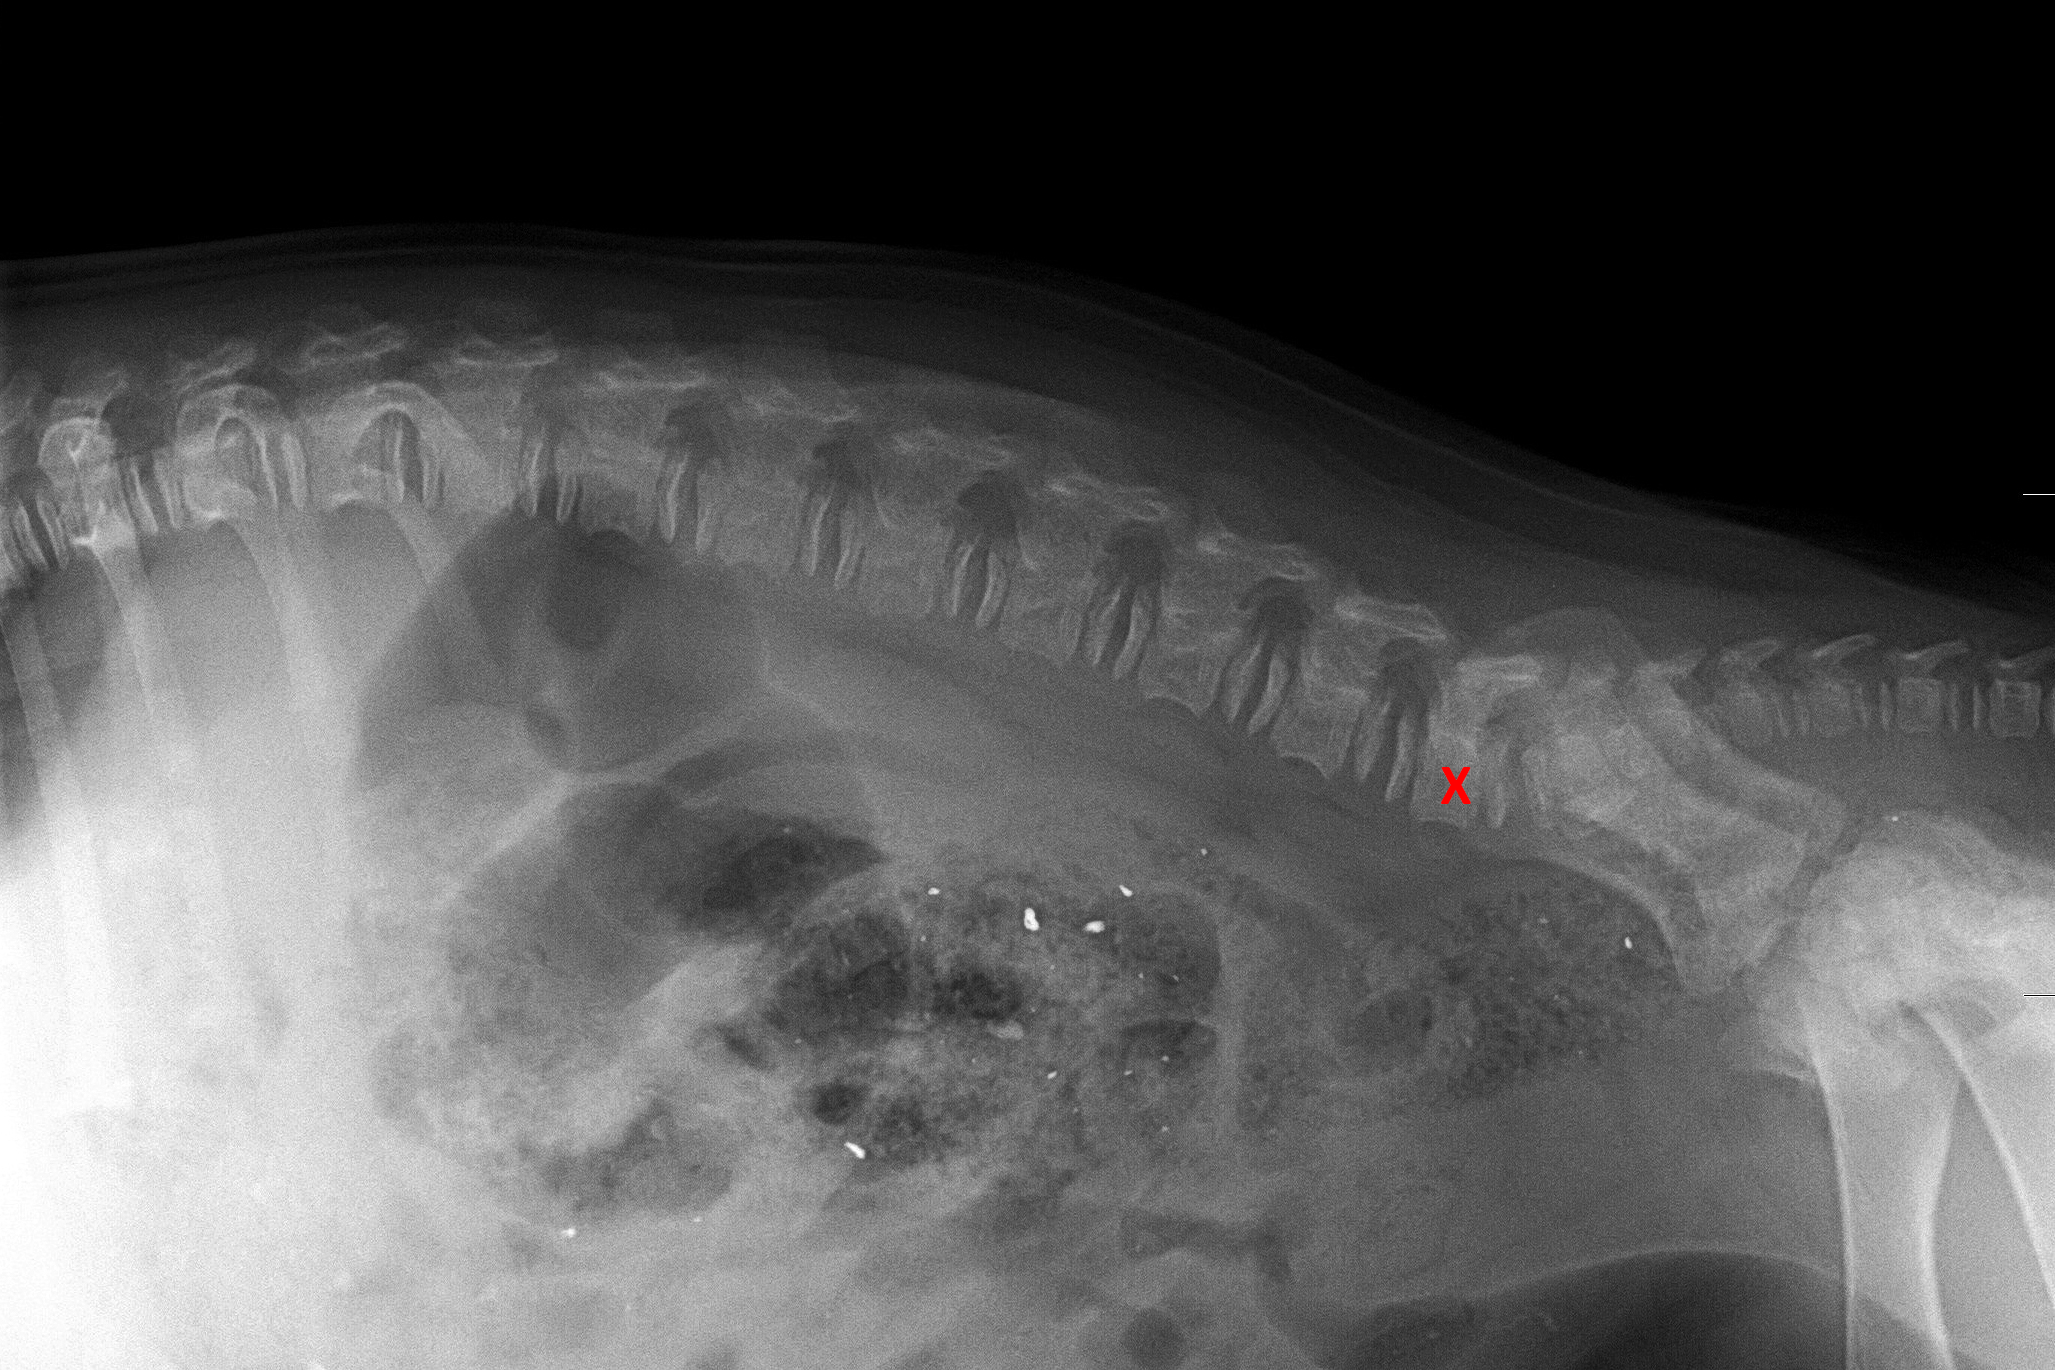

(5) 7 měsíců lat

(5) typ 3 páteř VD